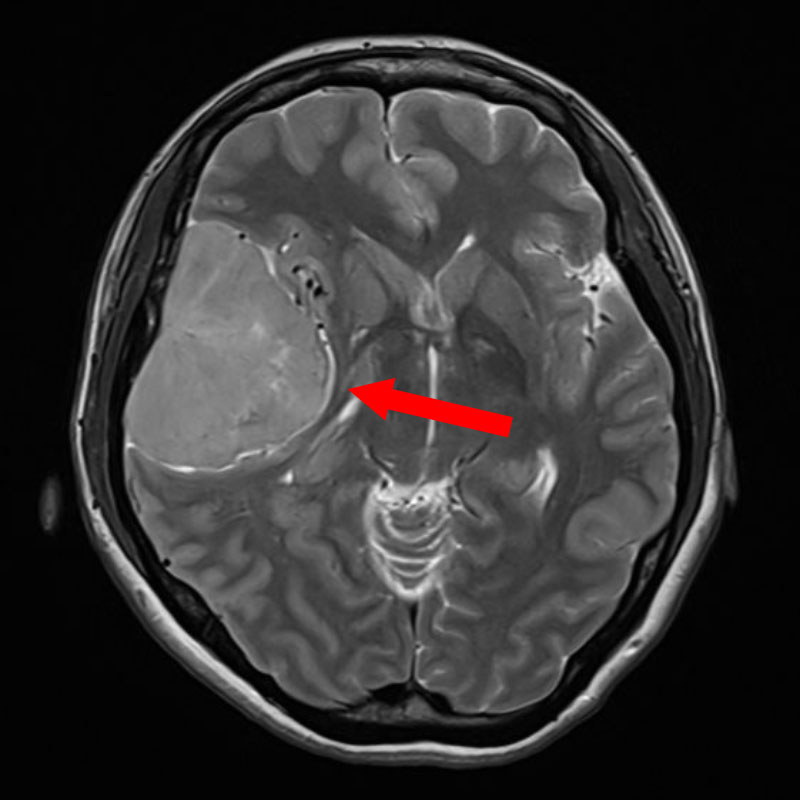

右側頭葉神経膠腫

頭蓋内腫瘍摘出術